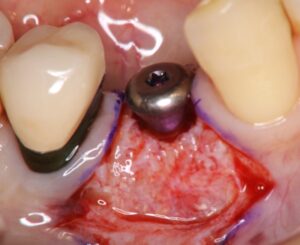

今回の症例では、インプラント埋入直後はネジ山の大部分が露出した状態でしたが、同時に骨造成手術を行ったことで、6か月後の2次手術時には良好な骨再生を確認できました。

インプラント埋入・骨造成手術から6か月後